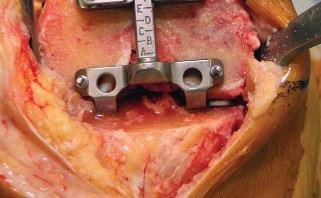

يركز هذا النهج على استخدام فتحة المفصل شبه الرضفية الإنسية المحدودة (Limited Medial Parapatellar Arthrotomy) وشق العضلة الرباعية المحدود، وهو جزء من مجموعة من الأساليب المعدلة التي توفر وصولاً ورؤية محدودين، ولكن يمكن تحويلها إلى نهج تقليدي إذا لزم الأمر. هذا يعني أن الجراح يمكنه البدء بتقنية أقل توغلاً، مع الاحتفاظ بالقدرة على التكيف إذا كانت الحالة تتطلب رؤية أوسع.

يُعد النهج شبه الرضفي الإنسي المحدود في جراحة استبدال مفصل الركبة الكلي بالحد الأدنى من التدخل الجراحي خيارًا مألوفًا ومتعدد الاستخدامات، وقد تطور مع إضافة أدوات أصغر وأكثر كفاءة. يتميز هذا النهج بقدرته على التكيف مع مجال العمليات المحدود في الركبة، مما يسمح بتشريح جراحي محدود دون المساس بالإجراء أو النتائج.

يتمتع الأستاذ الدكتور محمد هطيف بخبرة واسعة في جراحات استبدال مفصل الركبة، وهو ملتزم بتقديم أحدث التقنيات لمرضاه في صنعاء. يحرص الدكتور هطيف على اختيار المرضى المناسبين لهذه التقنية بعناية فائقة، مع الأخذ في الاعتبار جميع العوامل لضمان تحقيق أفضل النتائج الممكنة. إن تركيزه على التفاصيل الدقيقة واستخدامه لأحدث الأدوات يجعله مرجعًا موثوقًا به في هذا المجال.

معايير اختيار المرضى للتدخل الجراحي المحدود

ليس كل المرضى مرشحين لعملية استبدال مفصل الركبة بالحد الأدنى من التدخل الجراحي. يعتمد نجاح هذه التقنية بشكل كبير على اختيار المريض المناسب. يولي الأستاذ الدكتور محمد هطيف اهتمامًا خاصًا لهذا الجانب، حيث تشير الخبرة إلى أن بعض المرضى يستفيدون أكثر من غيرهم.